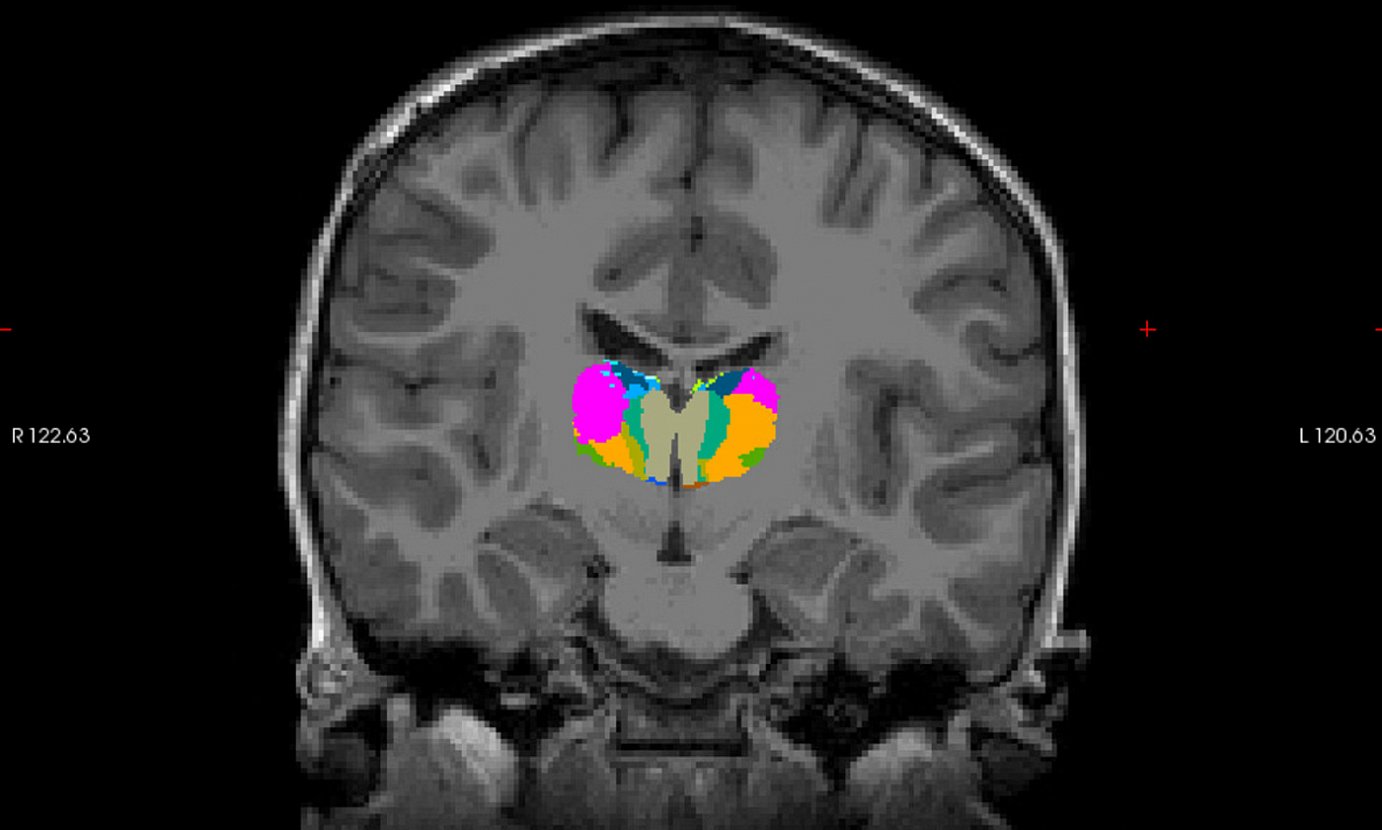

Irakurketari lotutako ariketa zehatzagoak egingo dituzte, bai papera eta arkatza erabiliz, bai tabletak baliatuz, eta baita erresonantzia magnetikoa ere. Erresonantzia magnetikoaren bidez, haur eta nerabeen garunaren funtzionamendua ikusiko dute. «Erresonantzia funtzionalaren ezaugarria da bide ematen digula jakiteko ea gure garunak nola erreakzionatzen duen ariketa batean», Aierberen esanetan.

Neuropsikologoak zehaztu duenez, «neurobiologia arloan, garun azala aztertu izan da gehienbat, garunaren kanpoko aldea». Azken urteetan, ordea, gero eta garrantzi handiagoa ematen ari zaie garun azalaren azpian dauden guneei, «fisikoki garunean sakonago daudenei». Horietako bat da talamoa (hiru zentimetro ingurukoa eta obalo formakoa), eta Dysthal proiektuan garrantzi handia emango diote. Hain zuzen, talamoaren eta garun azalaren arteko loturak aztertuko dituzte, eta «ea lotura horrek parte hartzen duen irakurketa prozesuan». BCBLko ikertzaileek uste dute baietz, eta eragina nolakoa den eta zenbaterainokoa den jakin nahi dute.

Talamoaren eta garun azalaren arteko loturak aztertuko dituzte, eta «ea lotura horrek parte hartzen duen irakurketa prozesuan».